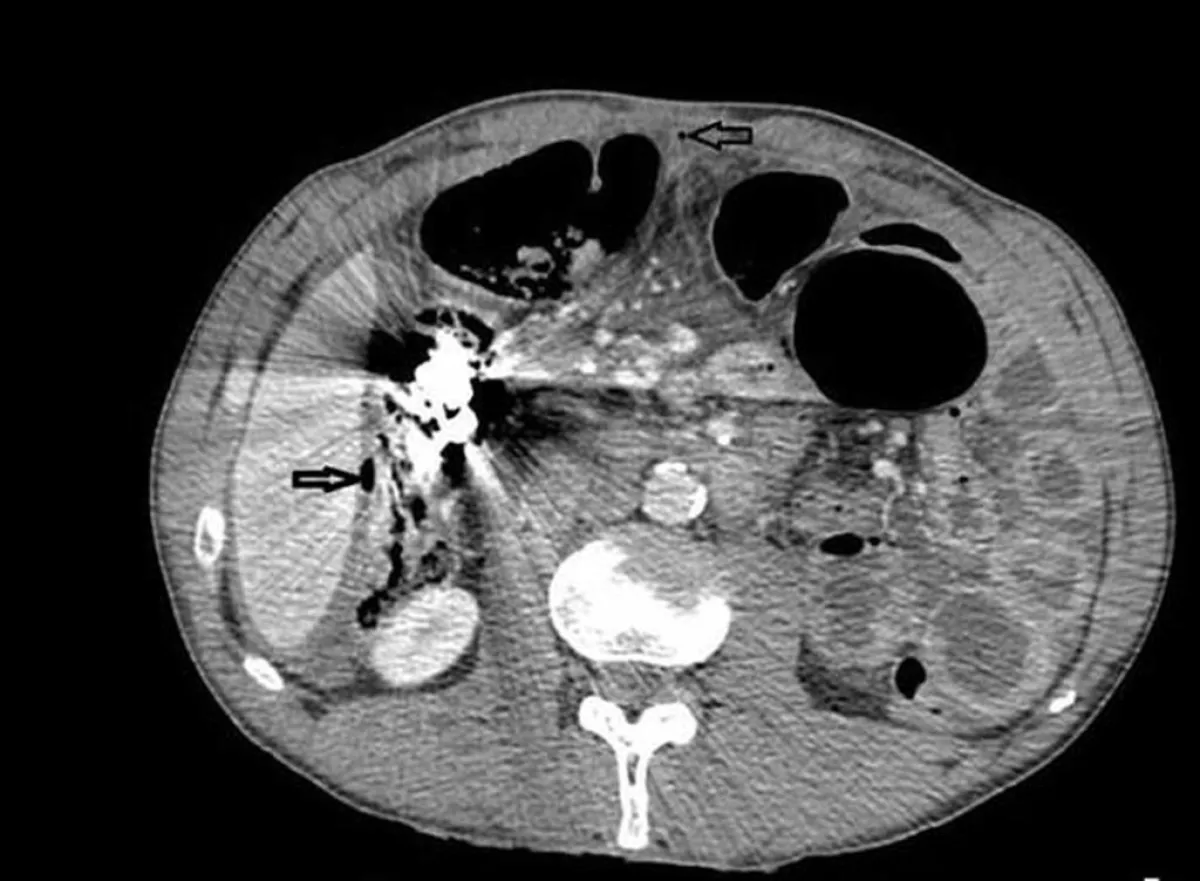

وقال الطبيب بريانك شارما، وفقًا لـ«روسيا اليوم»، عند إجراء التنظير لمعدة المريض: «صدمنا فعلاً؛ لأننا شاهدنا هناك العديد من النقود المعدنية والمسامير والبراغي والصامولات وغيرها».